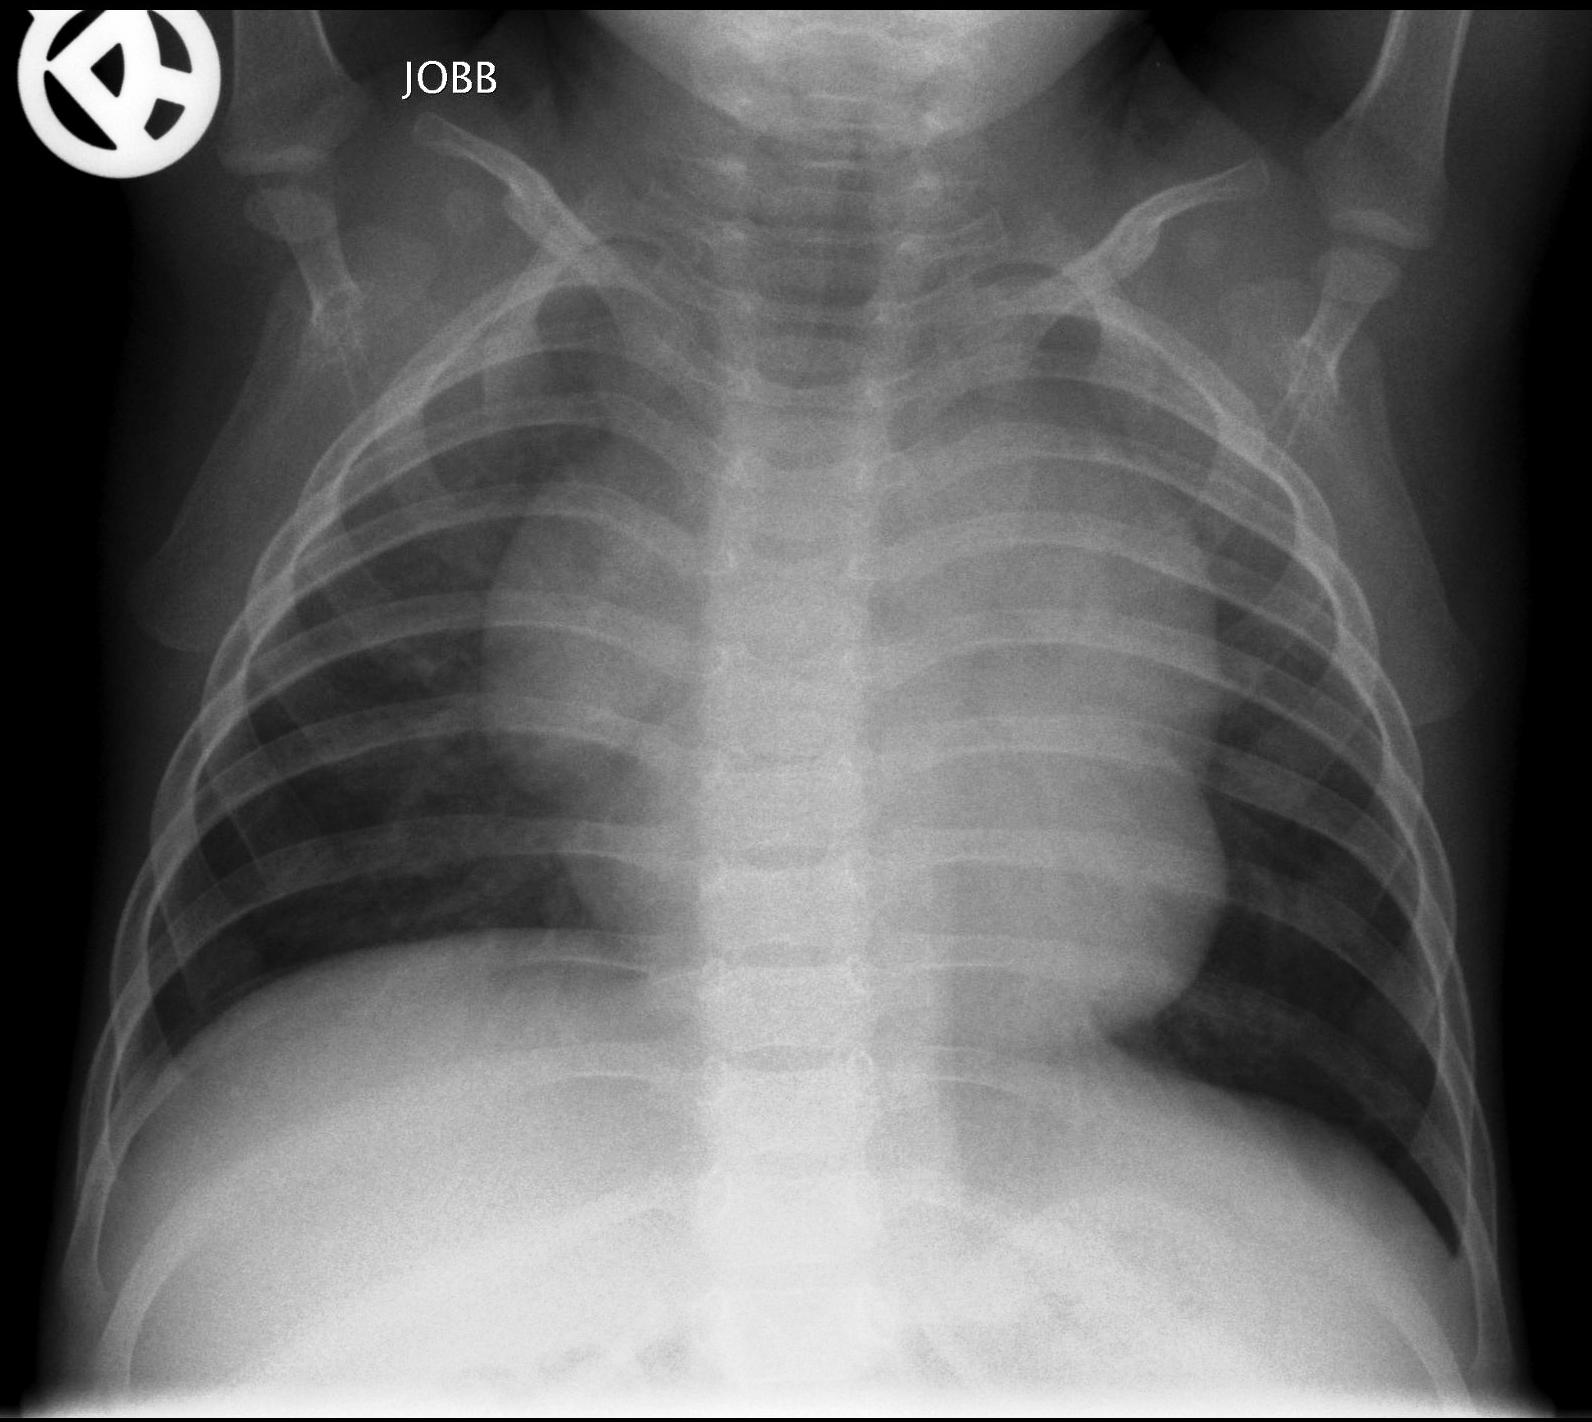

Normal newborn lungs: a newborn’s chest goes through some fundamental changes during the first days of extra-uterine life. The heart is relatively rounded, characterized by the dominance of the right side. The cardio-thoracic index taken in a mid-inspiratory state is between 0.55-0.62. Expiratory state can lead to diagnostic mistakes.

Bony thorax: the ribs are horizontal and the sagittal and horizontal diameters of the chest are very close to each other.

1.b. Inspiratory state, the lung is transparent, the heart is normal sized. Ribs run horizontally in infants.